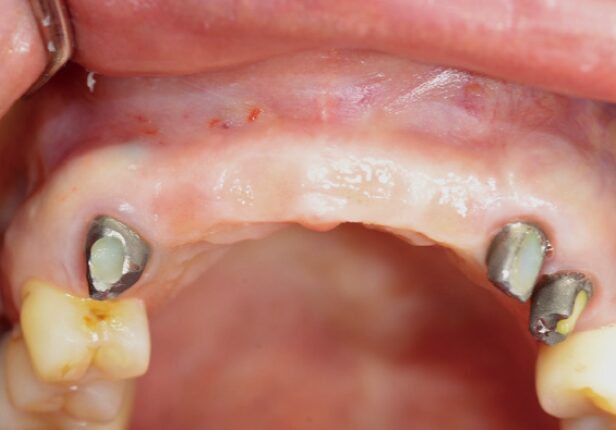

Before surgery